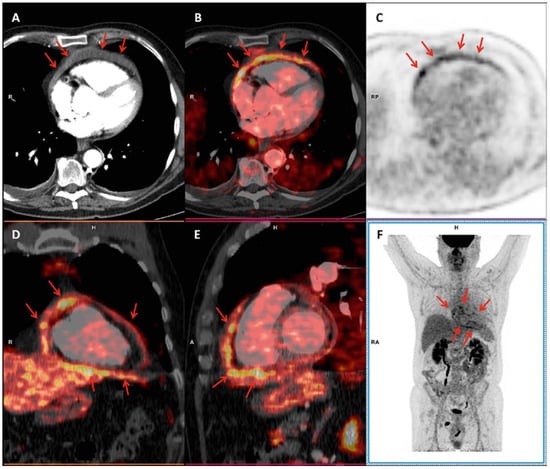

PET images showed several areas of increased radiotracer uptake around the heart, corresponding to a mild pericardial effusion on CT images (Figure 1). This “ring of fire” sign on PET/CT images represents increased metabolic activity around the heart and suggested the presence of acute pericarditis.

Figure 1.